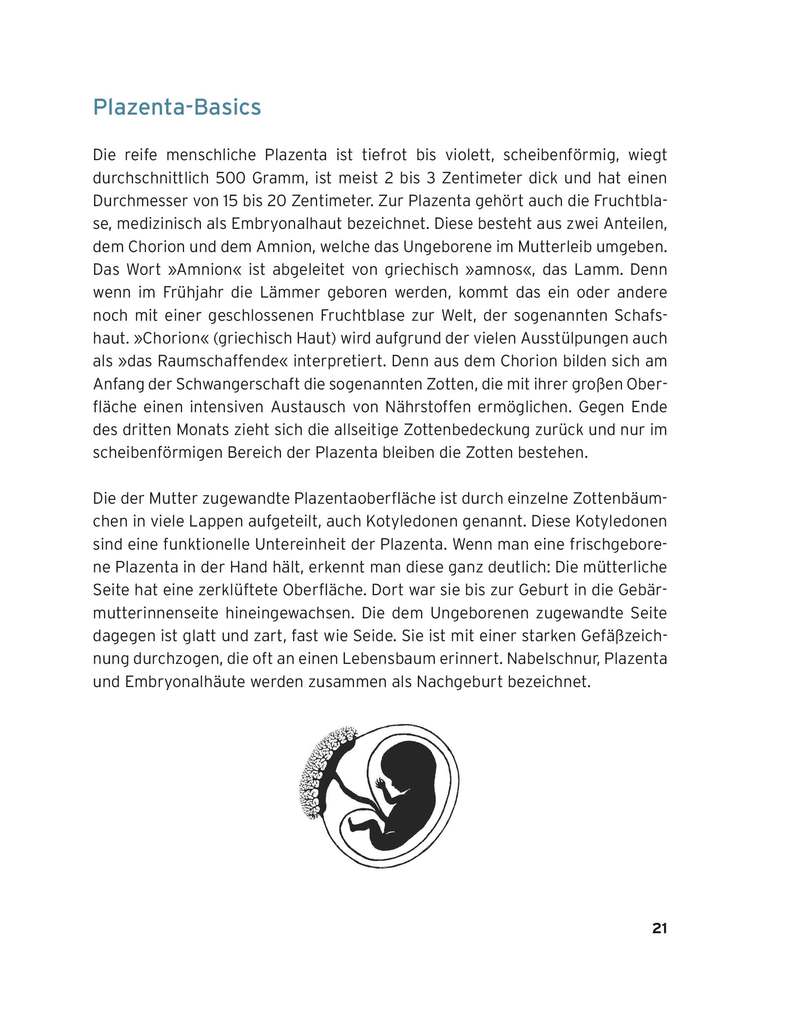

Alles über das Wunderorgan: Funktion in der Schwangerschaft, Bedeutung für die Mutter und integrative Verwendung als Heilmittel Die Plazenta ist eine wahre »Alleskönnerin«: In der Schwangerschaft leistet sie Erstaunliches für Kind und Mutter. Nach der Geburt findet sie auf viele Arten Verwendung, unter anderem als Heilmittel im Wochenbett. Doch wie genau funktioniert die Plazenta? Wie versorgt und schützt sie das Kind im Mutterleib? Und kann sie nach der Geburt bei mütterlichen Gemütsschwankungen oder Milchbildungsstörungen helfen? Die Ärztin Sophia Johnson und die Biologin Jana Pastuschek beschäftigen sich wissenschaftlich mit diesem komplexen Wunderorgan. Sie haben Hormone, Spurenelemente und Mikroorganismen in der menschlichen Plazenta untersucht, um der Frage auf den Grund zu gehen: Ist das die Wunderpille fürs Wochenbett? In diesem Buch stellen die Autorinnen neueste Ergebnisse aus der Forschung vor. Unterhaltsam und verständlich führen sie in das Plazenta-Universum ein und benennen medizinische, historische und kuriose Fakten. Sie widmen sich ausführlich dem Thema Plazentophagie (Plazentaverzehr) und geben praktische Tipps und Rezeptvorschläge von der Plazenta-Kapsel bis zum Smoothie. Ergänzt wird diese Darstellung aus medizinwissenschaftlicher Sicht durch Erfahrungsberichte von Frauen, die ihre Plazenta als Heilmittel genutzt haben.